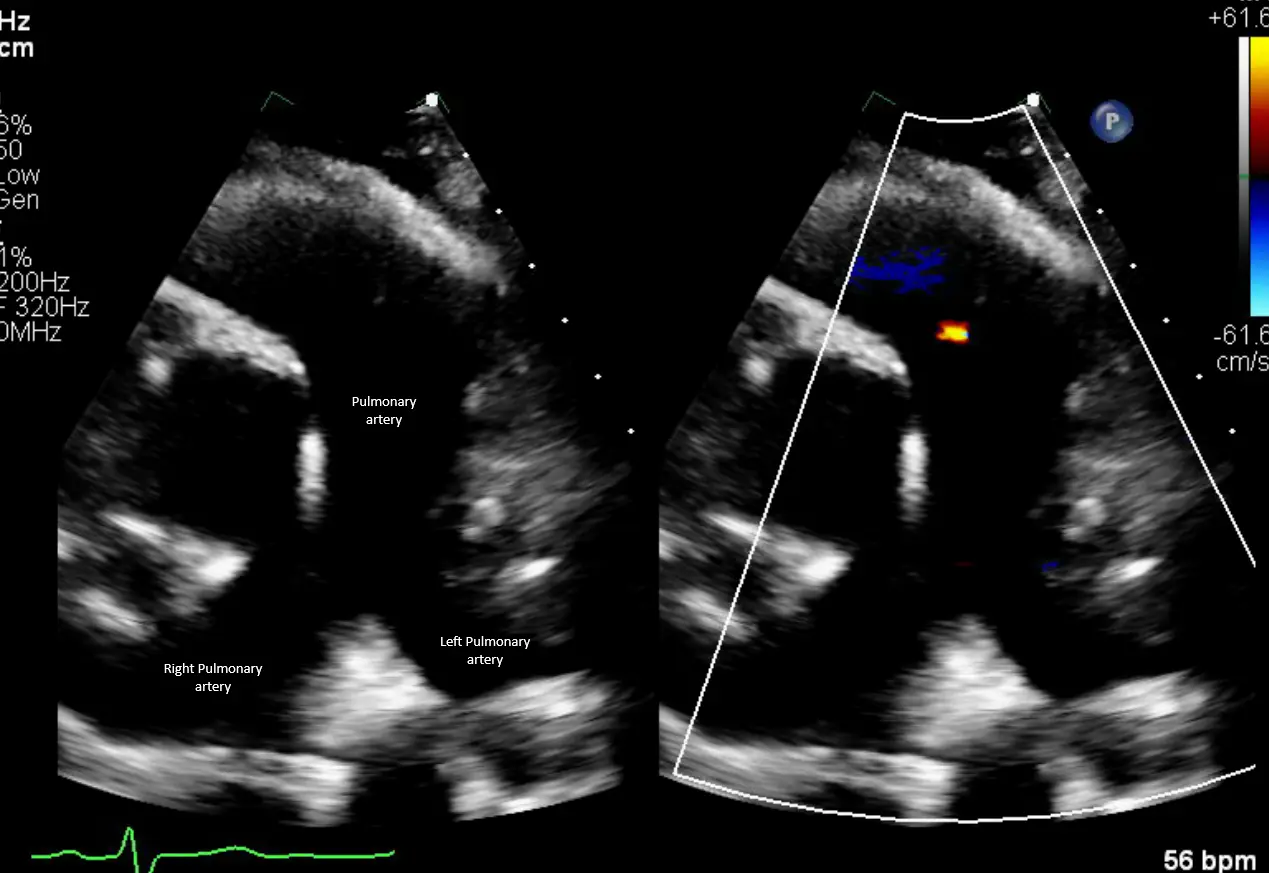

Nice view of the pulmonary artery with bifurcation in the short-axis RVOT view on TTE